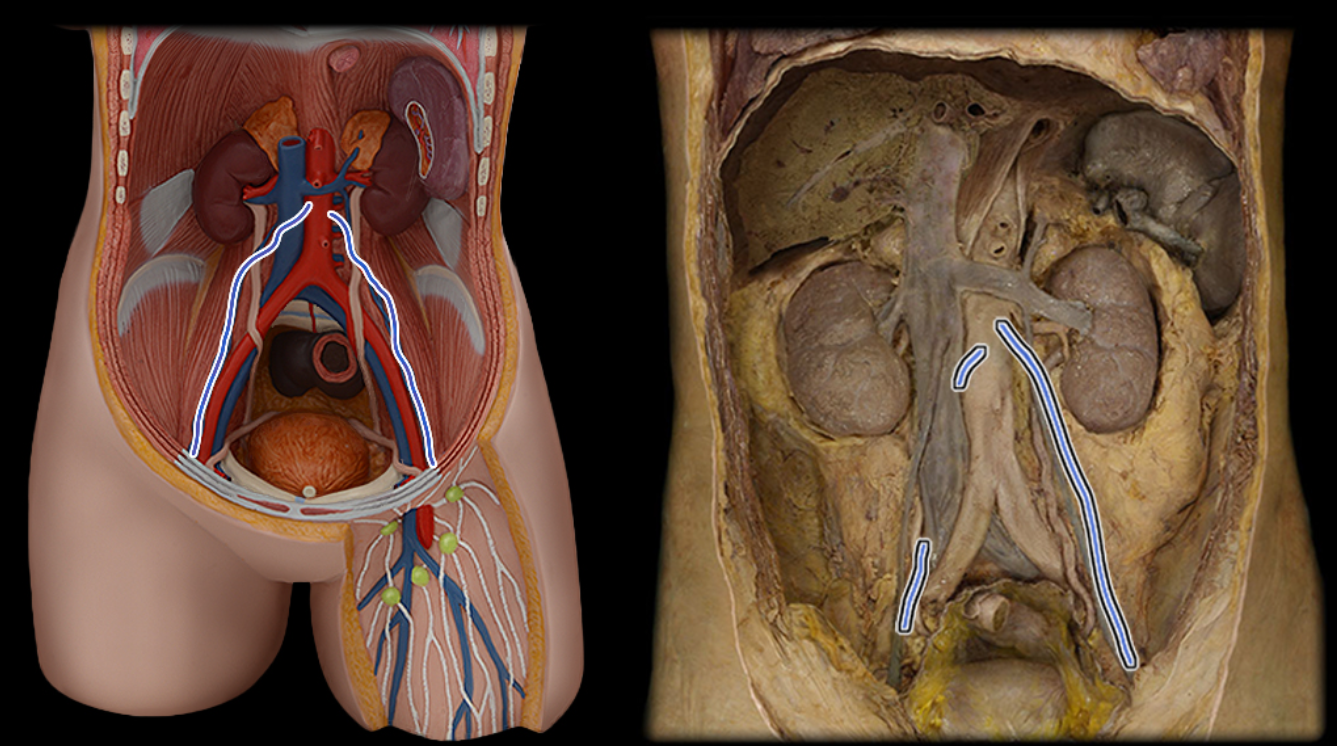

Abdominal aorta

Common iliac a.

Common iliac v.

External iliac a.

External iliac v.

Femoral a.

Femoral v.

Gonadal a.

Gonadal v.

Great saphenous v.

Inferior vena cava

Lumbar a.

Lumbar v.

Renal a.

Renal v.

Superior mesenteric a.